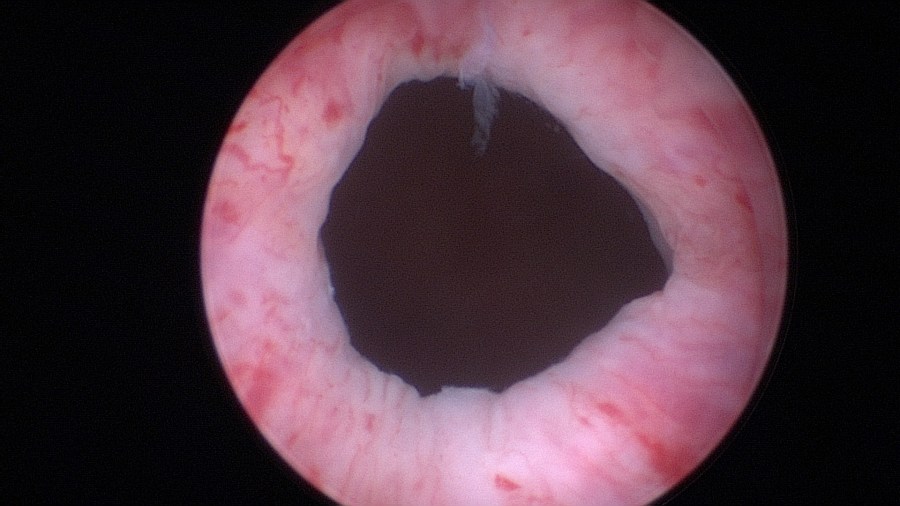

Begin injecting Bulkamid® hydrogel.

Image after injecting 0.5ml at the 12 o’clock position.

Rotate the sheath and inject now at the 3 o’clock position. Again notice that the bevel of the needle faces the center of the lumen and that an adequate “mucosal shelf” is formed.

Image after injecting the second 0.5ml of Bulkamid® hydrogel at the 3 o’clock position.

The needle is shortly removed and the second syringe of 1ml Bulkamid® hydrogel is loaded. Find the exact location of the previous injections and continue with the next one at 9 o’clock.

Image after injecting the third 0.5ml Bulkamid® hydrogel at 9 o’clock.

Lastly inject the final 0.5ml of Bulkamid® hydrogel at the 6 o’clock position.

Final image of the mid-urethra after creating four depots of Bulkamid® at the 12, 3, 9 and 6 o’clock positions.